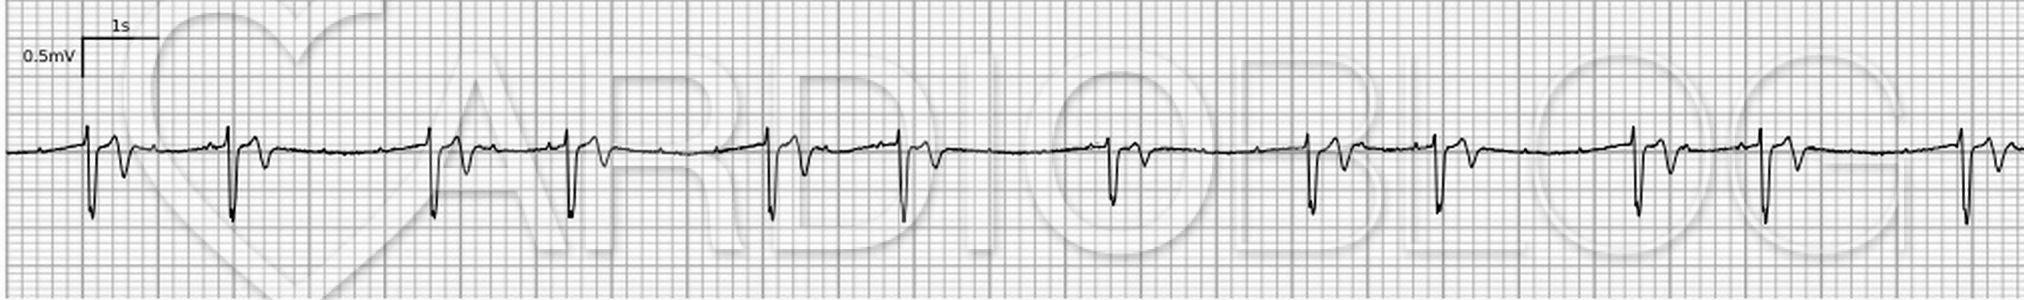

A nyáron ez a regisztrátum landolt a Cardioblog postaládájában. Méltó szezonkezdőnek. Indul a tizenhetedik évad. Mi látható rajta?

A klinikumról nem kaptunk információt. Csak ez az egycsatornás ritmuscsík áll rendelkezésünkre.

Feltűnő, hogy sokkal több a P, mint a QRS.

Ha szemügyre vesszük a rögzítés beállításait, akkor feltűnő, hogy a papírsebesség gyorsra van állítva. Ebből adódik, hogy a P-hullámok kicsikék, éles, rövid "huplikként" jelennek meg. Ugyan-emiatt a QRS-ek is keskenynek tűnnek, de valójában legalább 200ms-osak. (Az extrém széles QRS-ek okairól korábban ebben a feladványban értekeztünk.) A P-k frekvenciáján kívül (~75/perc) az állapítható meg, hogy csak nagyjából regulárisak. A morfológiájukról nem sok mondható. Még azt sem tudjuk, melyik elvezetésről van szó. Némi csúszkálás van a PP távolságokban: a regisztrátum elején a PP távolságok kicsit rövidebbek, mint a végén.

Ha megtaláltuk a P-hullámokat, azt vehettük észre, hogy annak ellenére, hogy a PP-távolság a ritmuscsíkon idővel némileg módosul (elején hosszabb, végén rövidebb), a PQ távolságok sosem változnak. A szigorúan, pontosan kétféle PQ távolság - egy rövidebb (~300ms) és egy hosszabb (~600ms) - stabilan, konstans végigkövethető. Tehát nagyon valószínű, hogy az összes QRS valamilyen úton-módon függ a P-hullámoktól. Ellenkező esetben ugyanis a PQ távolságoknak komolyabb variabilitást kellene mutatniuk a PP távolságok változásával. A felvetődő egyszerűbb magyarázat: például, hogy minden rövidebb RR távolságot junkcionális extrasystolék okoznak vagy például, hogy egy magasfokú AV-blokkban (6:1 blokkarány) minden hosszabb RR távolság junkcionális pótütés eredménye (minden ~300ms-al levezetett P hullámot követően (pl a 2.,4., QRS-ek), 2600ms-onként érkezik egy pótütés) nem lehetséges, mert ezekben az esetekben a PP-k változásakor a PQ-knak is módosulnia kellene. A pótütés teória azzal is cáfolható, hogy ez esetben a 7. QRS-nek is 2600ms-ra már meg kellene érkeznie, de itt az RR távolság 2800ms.

Olyan esetekben, amikor a QRS-ek csoportokban (ún. group beating) helyezkednek el, mindig jusson eszünkbe a Wenckebach periodicitás lehetősége (legyen az atrioventricularis vagy sinuatrialis szintű)! Most azonban sokkal több P-hullám volt, mint QRS, így ez nehezen volt elképzelhető.

Hacsaknem minden második P-hullámot gondolatban "eltüntettünk". Akkor kijött a minta egy 3:2-es (és a regisztrátum közepén egy ízben 2:1-es) blokkaránnyal.

Ez rávezethetett minket a megfejtésre, az úgynevezett "kétszintű AV-blokk" ritka fenoménjára. Az érthetőség kedvéért létradiagrammon ábrázoljuk a jelenséget: